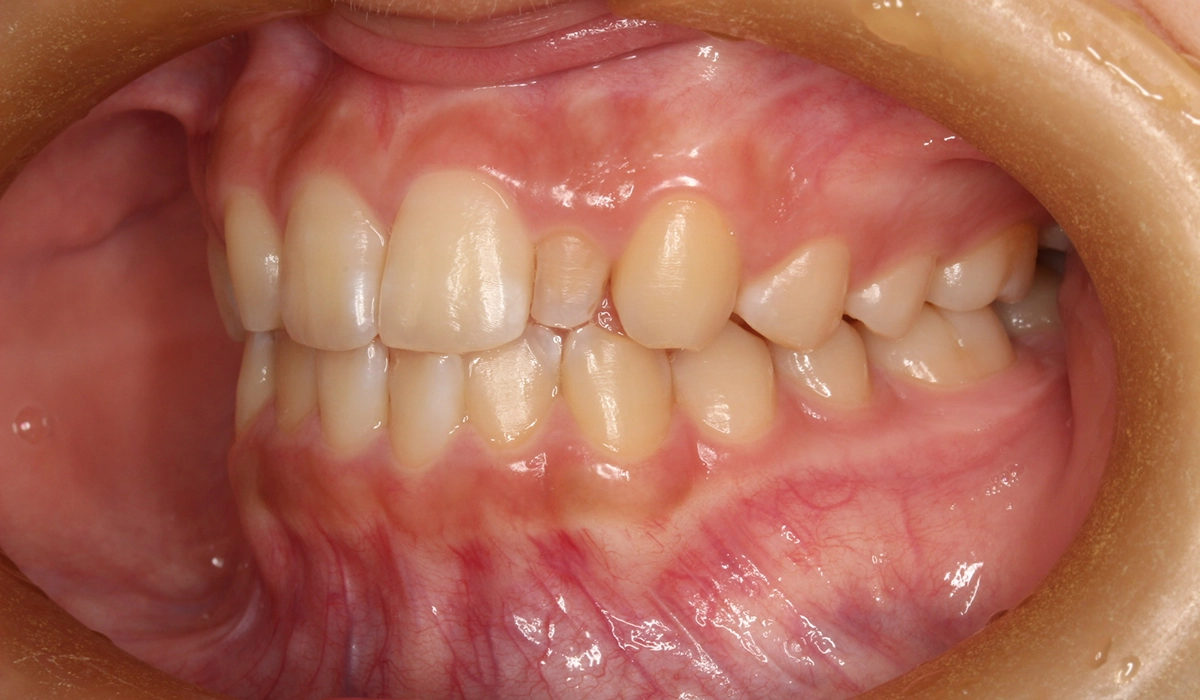

術前:右側

術後:右側